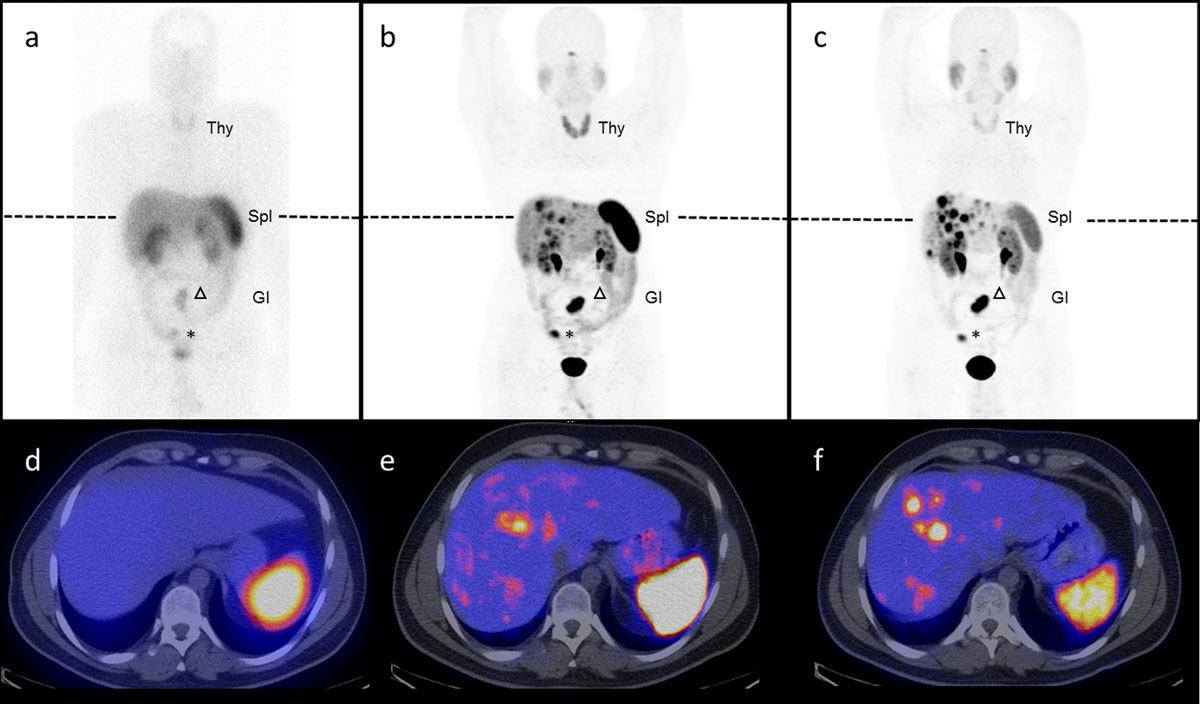

PET imaging with 68Ga-labelled somatostatin agonists is superior to somatostatin receptor scintigraphy [13, 14] using 111In-DTPA-octreotide or 99mTc-HYNIC-TOC and offers numerous advantages (fig. 3). It allows high-quality imaging with improved sensitivity as early as 45 minutes after injection of the radiotracer, provides higher spatial resolution and enables better absolute quantification of tracer uptake (determination of the standardised uptake value (SUV)). In addition, the radiation dose is less than one-half of that of 111In-DTPA-octreotide [15]. Therefore, the 2017 European Neuroendocrine Tumour Society guidelines recommend imaging of GEP-NET with SSTR PET/CT (e.g., 68Ga-DOTATOC or 68Ga-DOTATATE) whenever available [16].

Figure 3 Somatostatin-receptor targeting using 111In-DTPA-octreotide, 68Ga-DOTA-octerotide and 68Ga-DOTA-SSTR-antagonist. Head-to-head comparison of 111In-DTPA-octreotide scintigraphy and SPECT/CT (a,d) versus 68Ga-DOTA-TOC PET/CT (b,e), 2 SSTR agonists and 68Ga-OPS202 PET/CT (c,f), a novel SSTR2 antagonist, in a 32 year-old patient with well differentiated ileal neuroendocrine tumour G2. The primary tumour is in situ (asterisk) and there are a mesenterial lymph (arrow head) and multiple liver metastases. Note, in this otherwise stable disease, the increased number of liver metastases visible on the antagonist scans (c, f) due to an improved signal-to-noise ratio compared to the agonist (a and b) as well as the decreased liver, spleen (Spl), thyroid (T) and gastro-intestinal (GI) uptake.

Until recently, all somatostatin-based radiotracers used in the clinic for diagnostic (SPECT, PET) or therapeutic (PRRT) procedures in patients with NET were agonists. It was thought that the internalisation of the tracer is essential for a high accumulation and long-lasting retention of the radiotracer into the tumour cells. The paradigm shifted when in vitro and in vivo data showed that a higher tumour uptake and longer tumour retention could be obtained with radiolabelled SSTR antagonists without documented internalisation [38]. Based on in vitro studies, it is likely that radiolabelled SSTR antagonists exhibit a higher number of potential binding sites on the receptor, thereby increasing the tumour uptake [38, 39]. This was confirmed with autoradiographic studies on human tumour sections [40].

First-in-human studies in five patients with NET demonstrated the high potential of radiolabelled antagonist (111In-DOTA-BASS) for imaging and also PRRT [41] (fig. 3). Because of these promising results, PET tracers were synthesised with high affinity for SSTR2 [42]. A first antagonist (68Ga-OPS202, also known as 68Ga-NODAGA-JR11) for PET/CT has been successfully evaluated in a phase I/II clinical trial [43, 44], which shows the superior sensitivity of the antagonist, compared to the well-established agonist 68Ga-DOTA-TOC in a head-to-head intra-patient comparative study. The respective therapeutic radiotracer 177Lu-OPS201 (also known as 177Lu-DOTA-JR11) has shown 1.7 to 10.6 times higher tumour doses than 177Lu-DOTA-TATE (agonist) in four patients with progressive and metastasised NETs [45, 46] (fig. 3). Importantly, the amount of antagonist peptide administered may further enhance the therapeutic index. In fact, it was shown that increasing peptide mass decreases the background dose for a constant tumour dose [46].